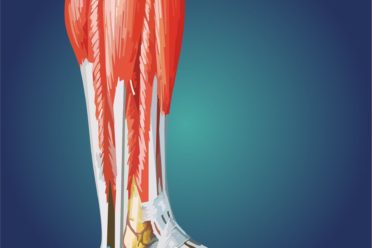

Czy kontuzja Roberta Lewandowskiego da się wyleczyć przed EURO? Kontuzje mięśniowe – naciągnięcia, naderwania i zerwania